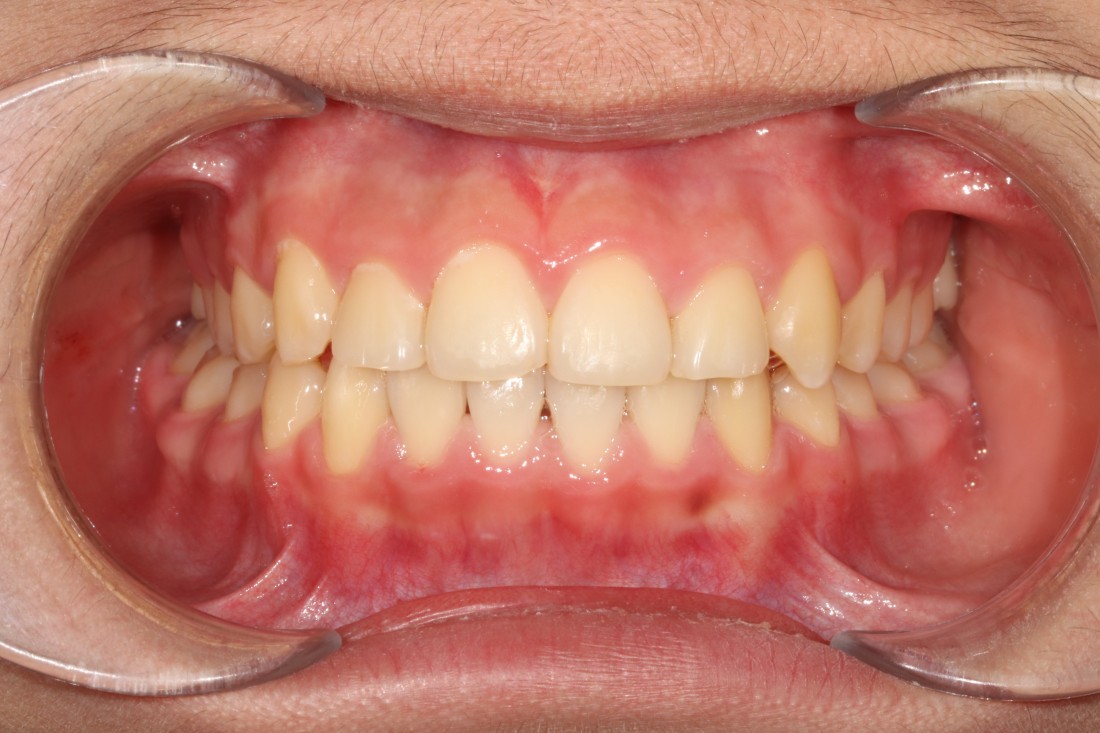

광주 덧니교정 치과는

대표원장인 제가 직접

다양한 교정 전/후 케이스를

공유하고 있습니다.

다양한 각도에서 촬영한

교정 전/후 사진을 직접 확인할 수 있어

광주 덧니교정 치과의

실력있는 진료를 증명하고 있습니다.

발치를 진행한 덧니교정이나

비발치 덧니교정 모두

다양한 케이스를 보유하고 있기 때문에

나의 구강구조와 비교해보면서

성공적인 교정치료 결과를

기대해보실 수 있습니다.